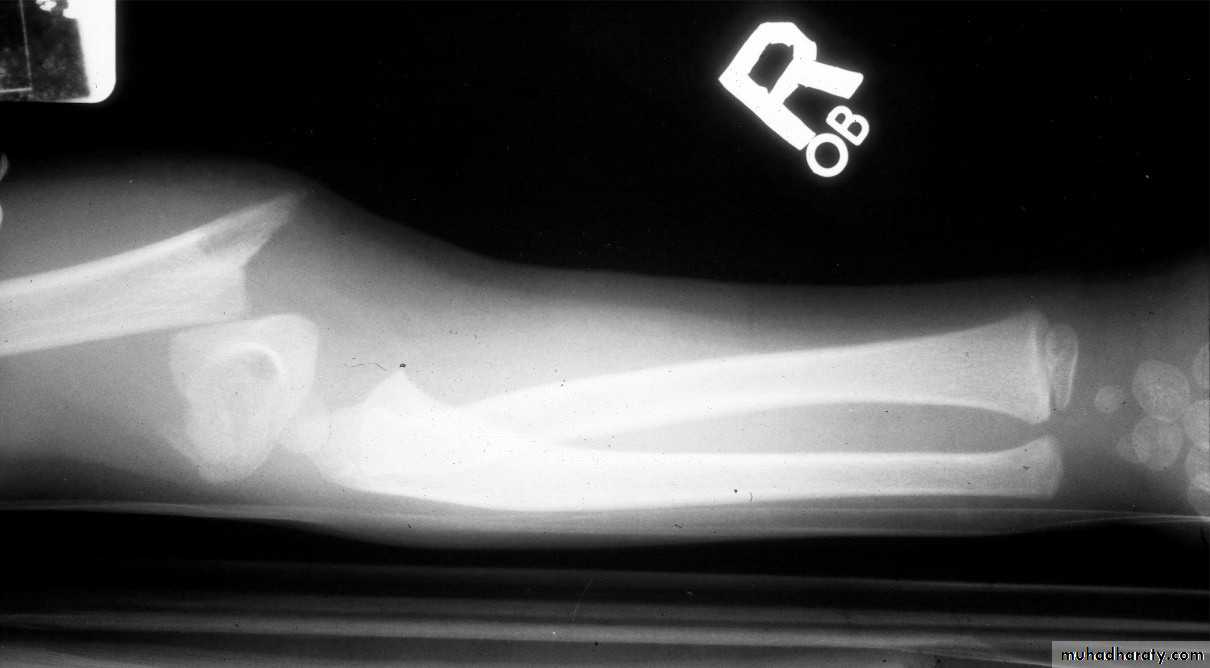

8 y.o. rolled over on an ATV

with mild closed head injuryClinical appearance

Only N-V deficit:

Anterior interosseous n. function weak

Radial A.

FCR Musc.Imaging Studies

How are we going to stabilize this boy’s fracture?

This is probably one of the few indication to use

Antegrade Flexible I M NailsOur Patient P.O.

Probably acts more

as an internal splintSix months post-operative

How is he doing clinically?